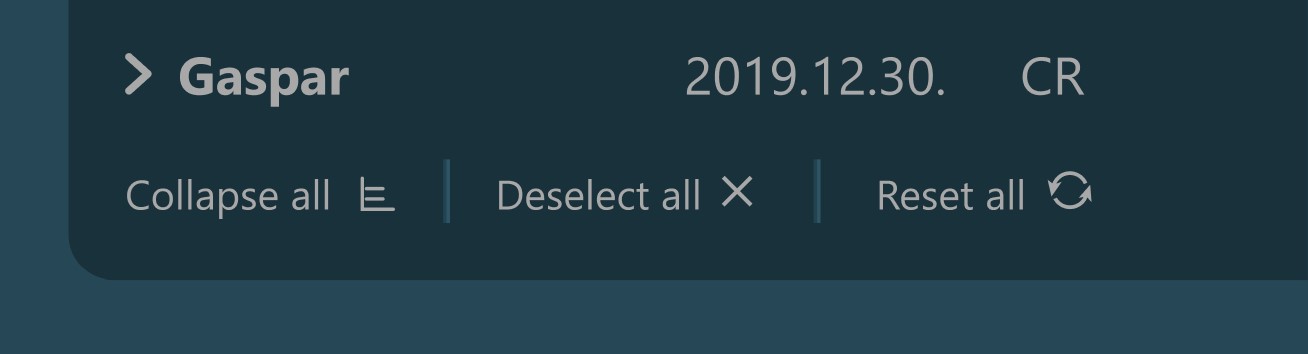

The Study List is located on the left side of the Study Browser window. All studies or patients (depending on the active mode) from the selected server will be displayed in the study list, based on the configuration of the DICOM servers.

Expand an item in the Study List by pressing the arrow next to the its name, which reveals its contents based on the DICOM hierarchy in the Study Browser.

Selecting a patient, study, or series from the Study List opens them and their contents in the Preview Pane, located on the right side of the Study Browser window. In the Preview Pane, the items are separated into sections based on their patient information.

The heading of each section shows the patient name, the latest related study date, patient sex, and owner name. Studies are shown as image groups containing the series as image previews. Each study is highlighted by its modality and date. To view the series description of each series, hover over the desired image preview.